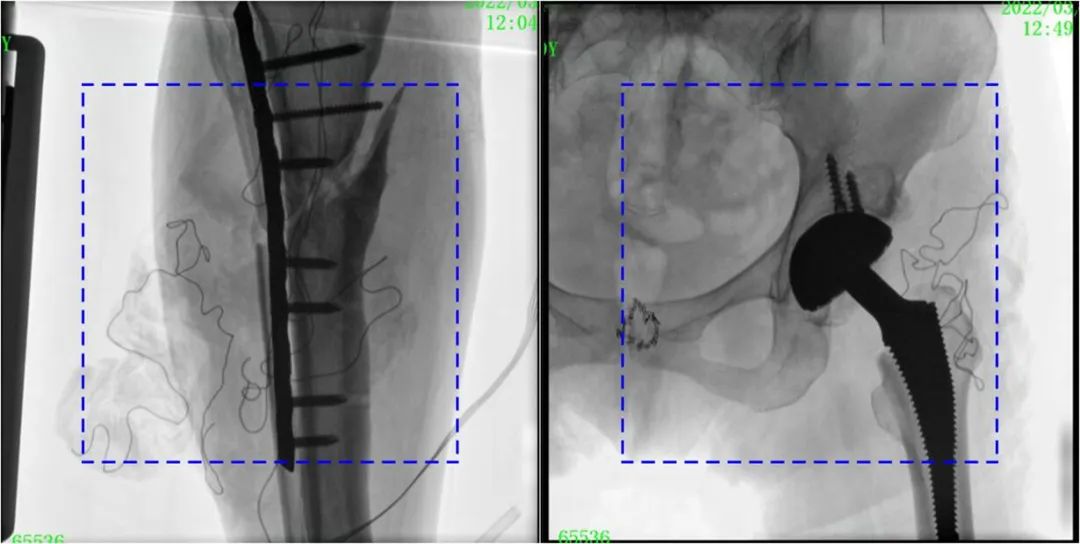

PLX119C臨床圖像與傳統(tǒng)圖像對比

注:藍色虛線內為傳統(tǒng)21CM×21CM平板的成像區(qū)域。